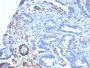

Smooth muscle myosin heavy chain (SM-MHC) is a cytoplasmic structural protein, which is a major component of the contractile apparatus in smooth muscle cells. Expression of smooth muscle myosin is developmentally regulated, appearing early in smooth muscle development, and is specific for smooth muscle development. Two isoforms of smooth muscle myosin heavy chain have been identified, designated MHC-1 and MHC-2. The antibody may be useful for the study of breast tumors as the presence of an intact layer of myoepithelial cells is an important feature, which may distinguish benign breast lesions and carcinoma in situ from invasive tumors.Primary antibodies are available purified, or with a selection of fluorescent CF® Dyes and other labels. CF® Dyes offer exceptional brightness and photostability. Note: Conjugates of blue fluorescent dyes like CF®405S and CF®405M are not recommended for detecting low abundance targets, because blue dyes have lower fluorescence and can give higher non-specific background than other dye colors.

Positive Control

Uterus or normal breast

Higher concentration may be required for direct detection using primary antibody conjugates than for indirect detection with secondary antibody|Immunohistology (formalin): 0.5-1 ug/mL for 30 minutes at RT|Staining of formalin-fixed tissues requires boiling tissue sections in 10 mM citrate buffer, pH 6.0, for 10-20 minutes followed by cooling at RT for 20 minutes|Optimal dilution for a specific application should be determined by user